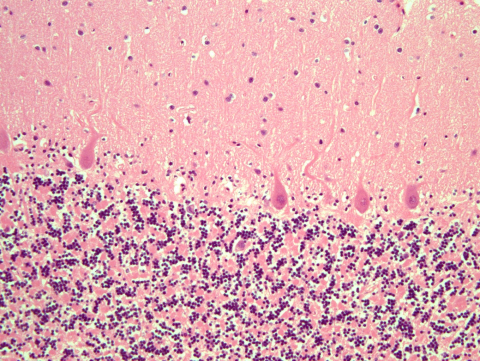

2. Genetic CJD

Genetic CJD

H&E